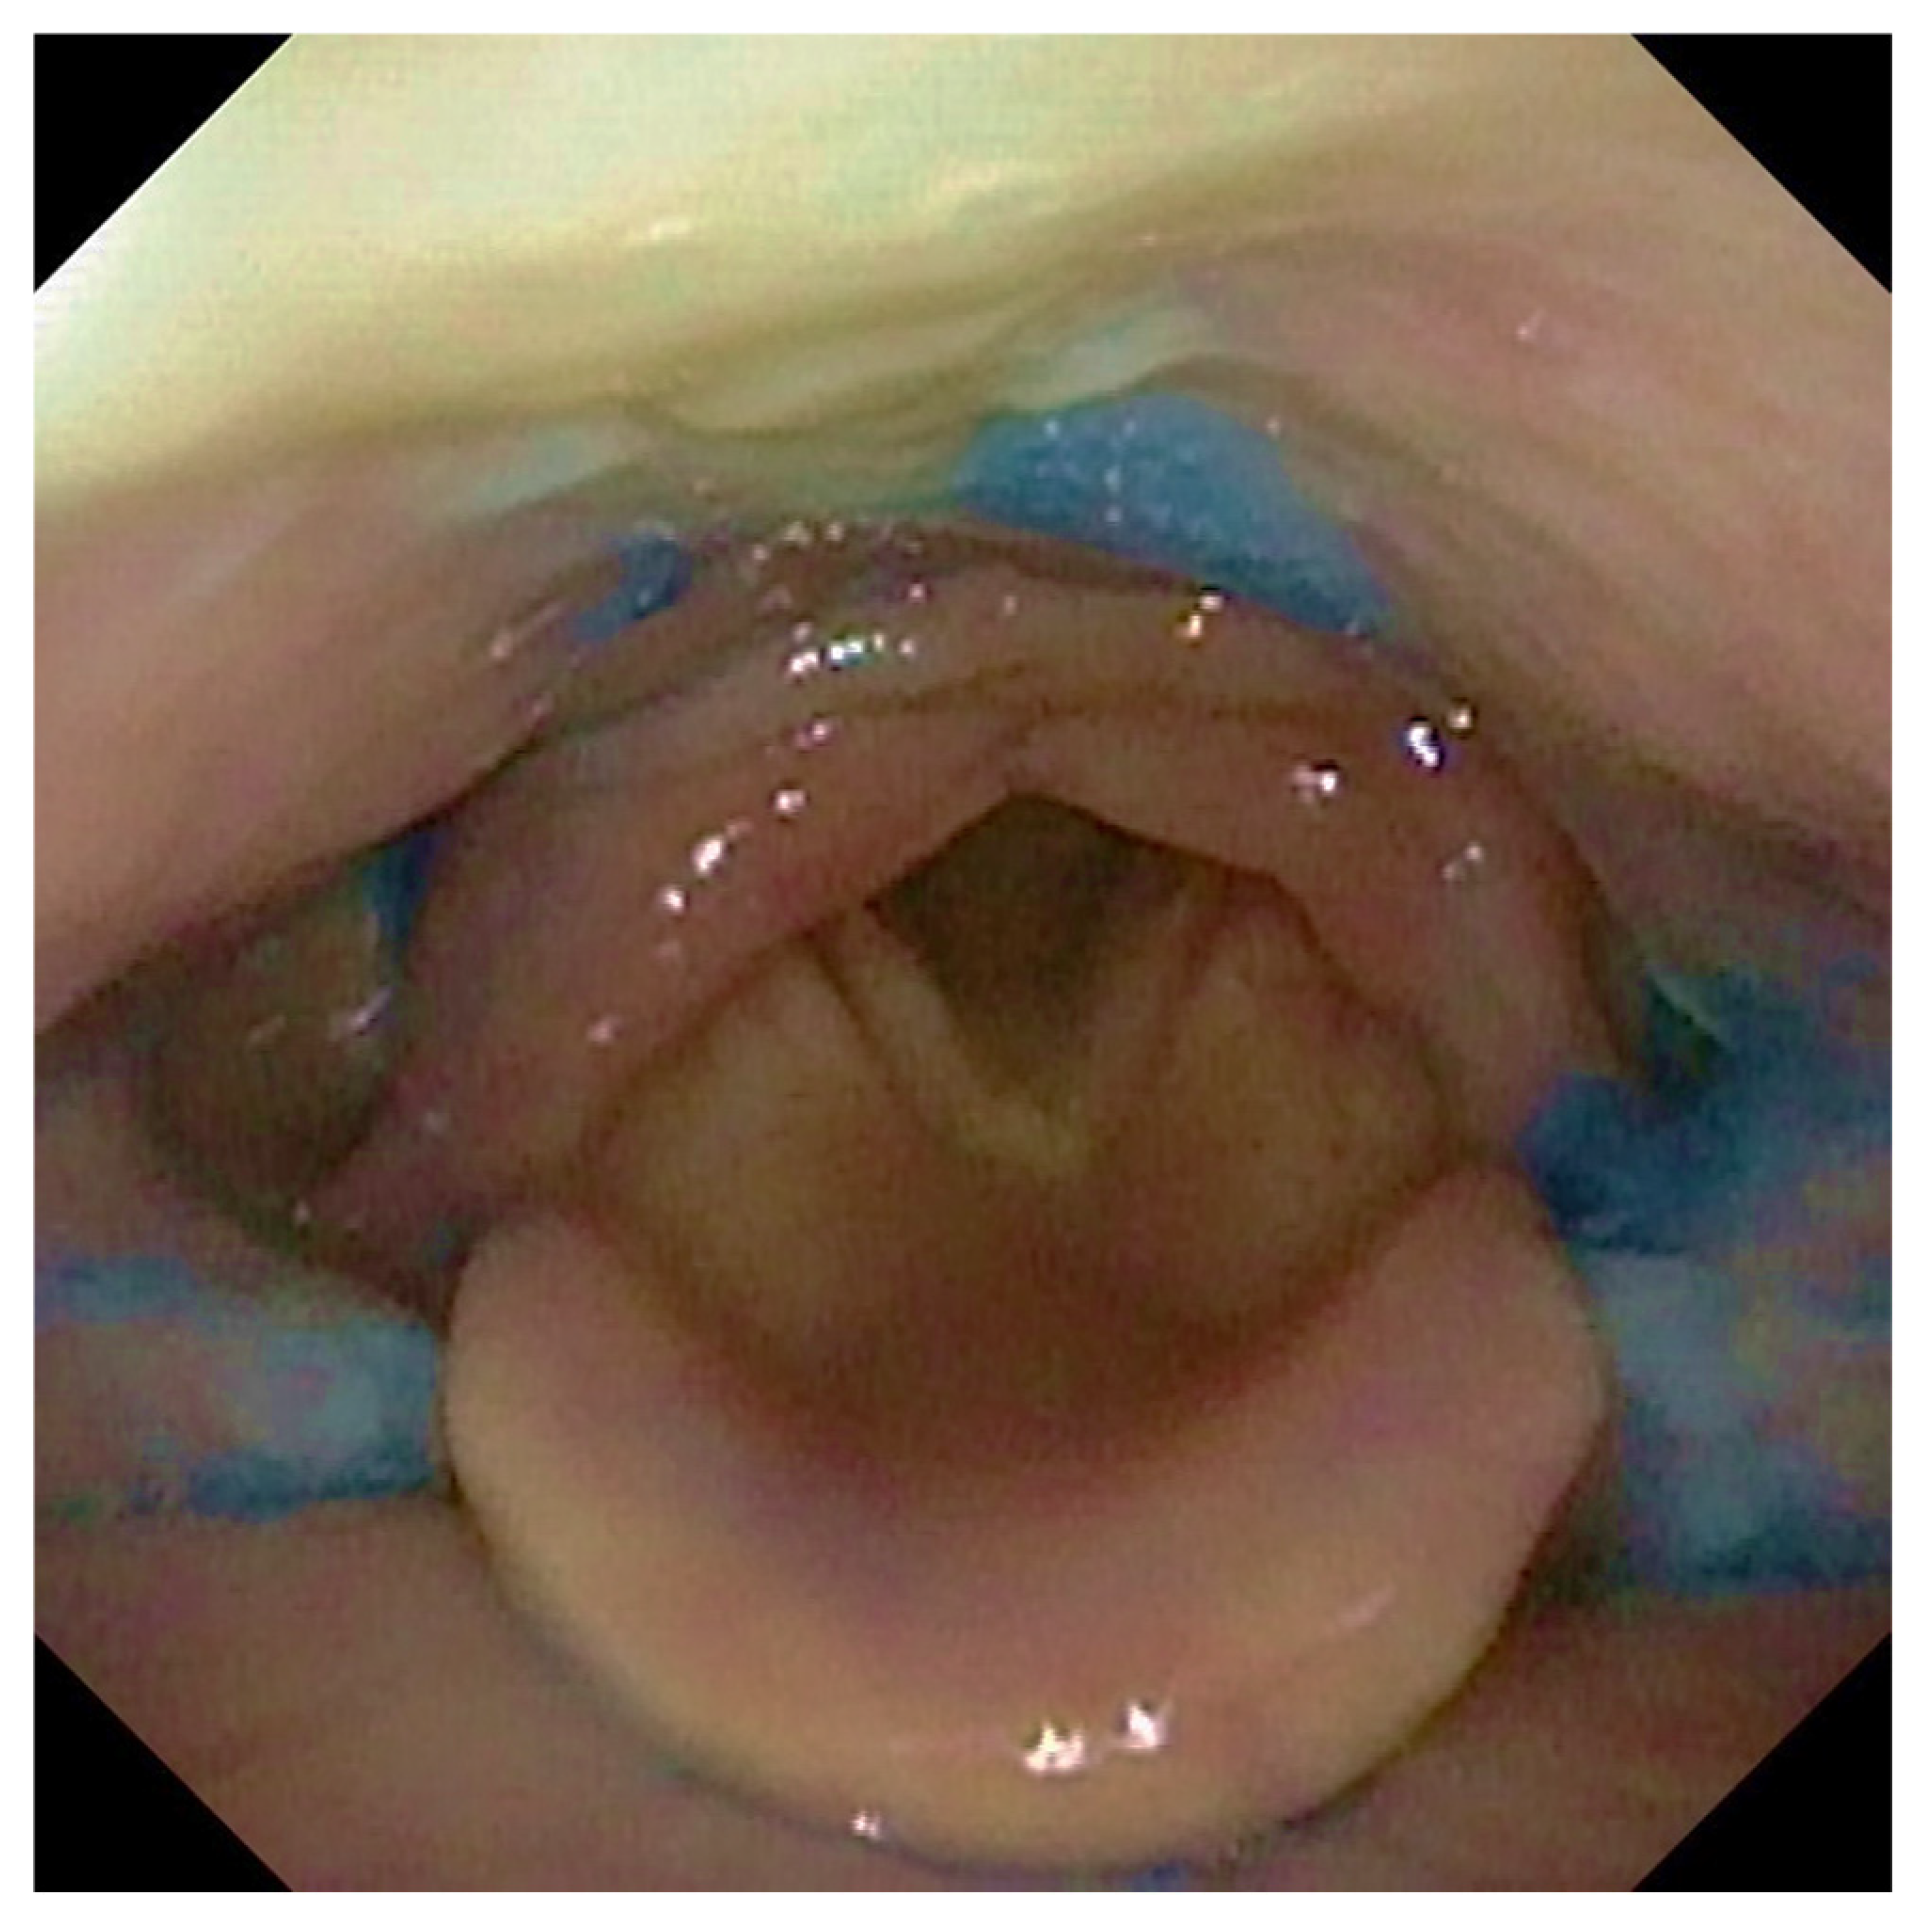

2.3. FEES Protocol